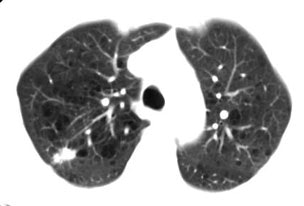

True positive Neotect exam: CT scan demonstrated an irregular nodule within the right upper lobe. Coronal Neotect image demonstrated abnormal tracer accumulation in the lesion. The lesion was surgically resected and found to be NSCLC. Case courtesy Dr. Jamie Montilla. |